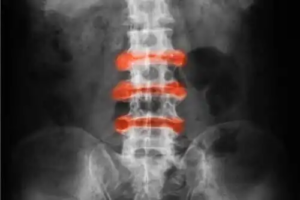

Ankyloserande spondylit är inflammatorisk artrit som förekommer främst i lederna i ryggen och bäckenet. De akuta symptomen och stelheten tenderar att förbättras med fysiska aktiviteter, och inaktivitet kan göra det värre.